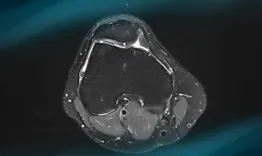

Frane Bukvić presents the case of a 34-year-old orthopaedic surgeon​ suffering from a symptomatic chondral ‘kissing’ lesion of patella and trochlea... How would manage this condition?

Management of chondral ‘kissing’ lesion of patella and trochlea

Frane Bukvić